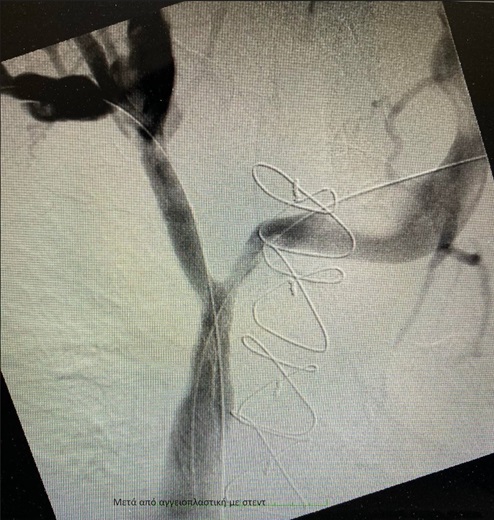

Η ομάδα της Α´ Αγγειοχειρουργικής κλινικής υπό την καθοδήγηση του Διευθυντή Αγγειοχειρουργού Νεκτάριου Γαλάνη και την πολύτιμη συνδρομή του Ακτινολόγου Βασίλειου Δημαρέλου και του Αναισθησιολόγου Δημήτριου Ζωσιμίδη, προχώρησε σε αγγειοπλαστική των πλέον στενωτικών σημείων των ανώνυμων φλεβών και της άνω κοίλης φλέβας υπό ακτινοσκοπική καθοδήγηση. Η προσπέλαση ήταν διπλή με παρακέντηση των μασχαλιαίων φλεβών αμφότερων των άνω άκρων και τοποθέτηση δίδυμων στεντ εύρους 12χλστ και μήκους 80χλστ στη δεξιά και αριστερή ανώνυμη φλέβα και την άνω κοίλη φλέβα, που αποκατέστησαν τη βατότητα των ανωτέρω αγγείων .

Παρά την εξαιρετικά απαιτητική διαδικασία, ο ασθενής έλαβε εξιτήριο τις επόμενες ώρες, με ήδη σημαντική βελτίωση του οιδήματος σε κεφαλή- τράχηλο και τα άνω άκρα, προς περαιτέρω ογκολογική θεραπεία.